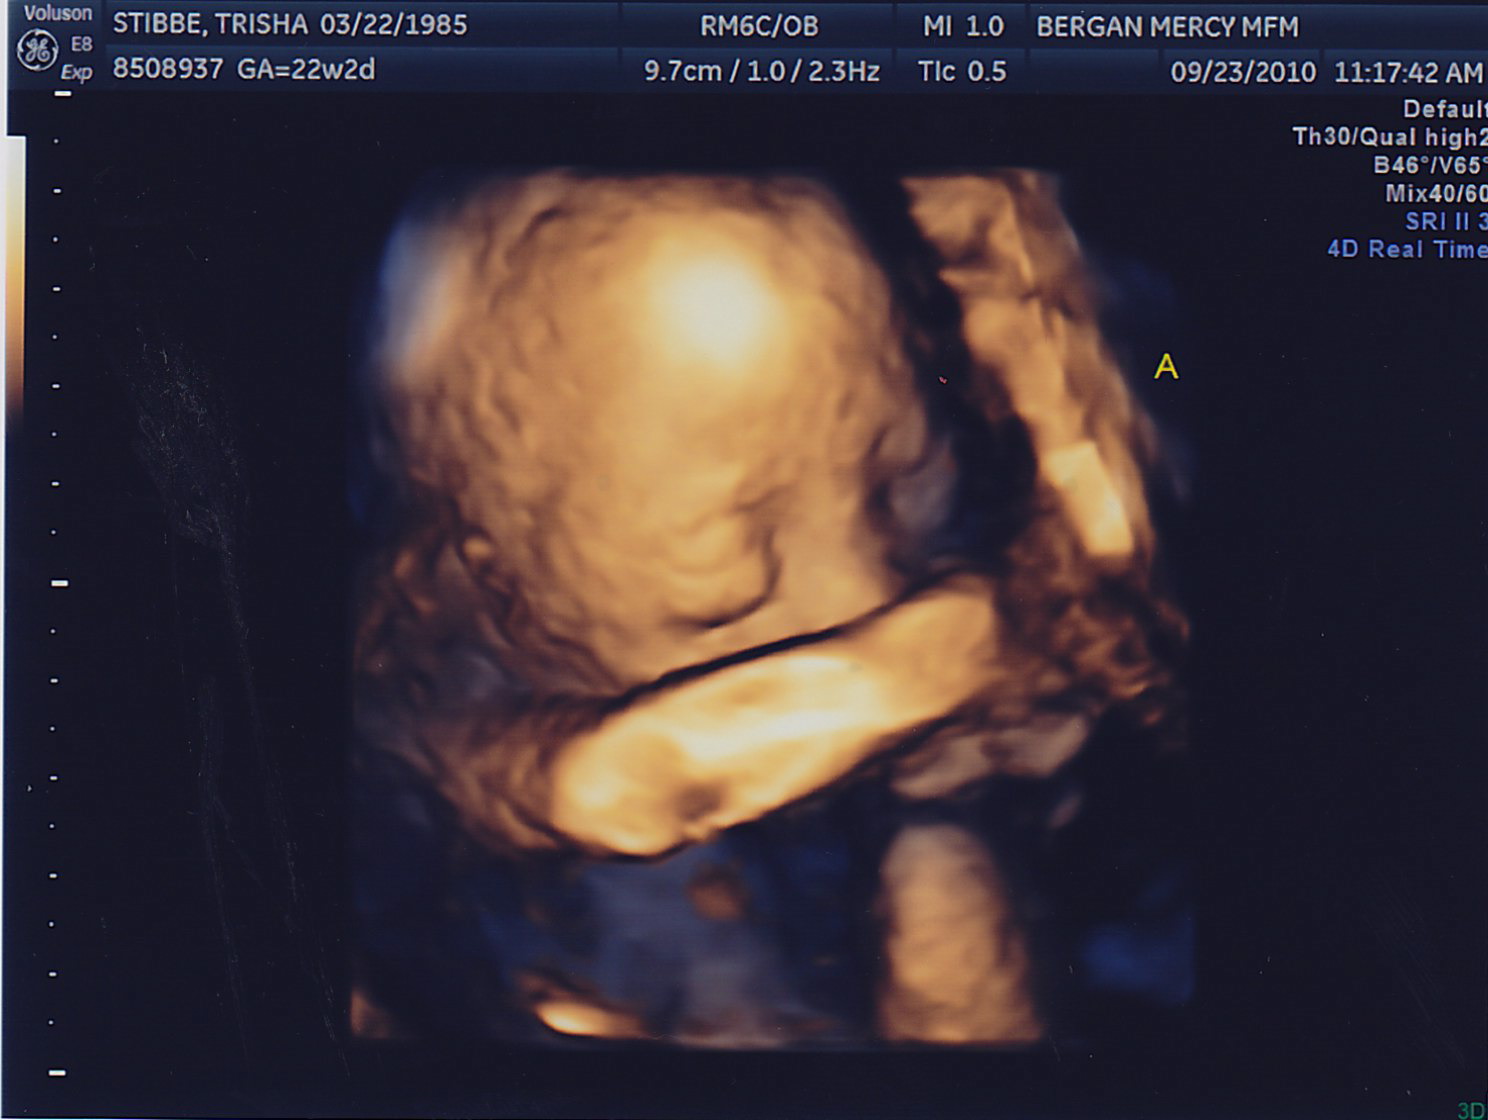

My sonographer Briana surprised me with 4D pictures! She was only able to get a good image of Baby A because Baby B is facing my back. One funny thing–for a while now they have both been on my right side and I could swear I looked lopsided. Then it started to kind of even out a little, and its because Baby A moved to the left! They’re finally learning to share 🙂 Last week they were both head down, and this week they’re both head up. Squirmy little guys.

Here are the little guys most recent pictures!

Hi Trish and Adam. Great pictures, I love the 4D’s. It’s amazing! It looks like Baby A is smiling in the one picture. He must be thinking about his Grandma. 🙂 Little B was being camera shy though. Little bugger.